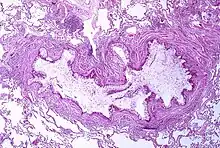

Astma skyldes en kronisk inflammation i luftvejene, som øger den omkringliggende glatte muskulaturs sammentrækningsevne. Dette er en af flere faktorer, som fører til anfald med indsnævrede luftveje og det velkendte symptom med hvæsende vejrtrækning. Indsnævringen vil oftest fortage sig med eller uden behandling.Luftvejene vil i visse tilfælde forandre sig.[16] Typiske luftvejsforandringer omfatter et øget antal eosinofile granulocytter og en fortykkelse aflamina reticularis. Luftvejenes glatte muskulatur kan blive kronisk forstørret med en øget mængde slimkirtler til følge.Andre berørte celler omfatter: T-celler, makrofager og neutrophile granulocytter. Andre af immunforsvarets dele kan også være involveret, herunder bl.a. cytokiner, kemokiner, histamin og leukotriener.[41]